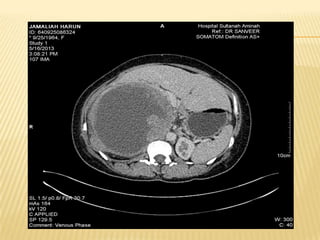

CT LIVER

IMAGING  Usg HBS Huge heterogenous cystic mass in the right liver lobe measuring > 20.5cm X 12cm.Presence of gallstone in GB.IHD and CBD not dilated Imp : suggestive of hydatid cyst with diffrential of amoebic liver abcess *** further history : h/o of multiple visits to egypt within past few years. Last visit was in feb 2013 whr she took local salad dish with grilled fish and snails delicacies